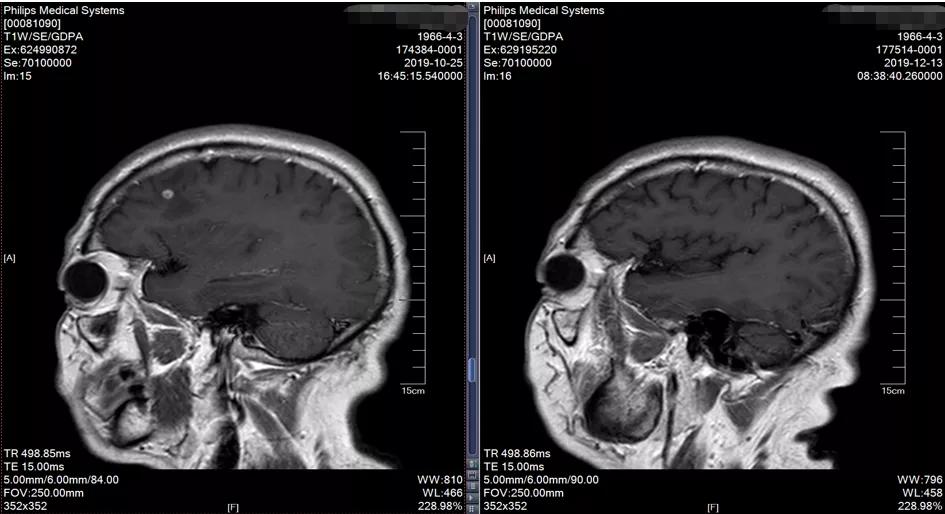

2019-10-25于广医一院行PET/CT检查考虑右上肺肺癌并右肺门、纵隔淋巴结转移。头颅MR:右侧额叶异常信号影, 考虑转移瘤。 双侧额顶叶散在缺血灶。

2019-10 头颅MRI示右额叶转移瘤,伴瘤旁水肿

2019-12-12头颅MRI示右侧额叶及左侧顶叶少许缺血灶,未见异常强化影